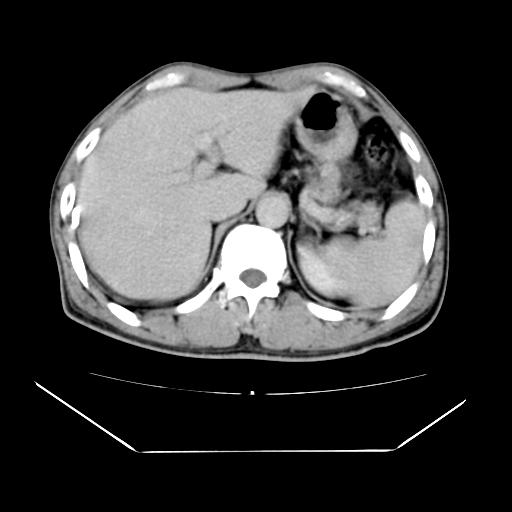

男性,55岁,外院体检afp明显升高,但b超未发现异常,否认乙肝病史。来我院ct增强。有延时扫描。

延时扫描完全充填,血管瘤

肝脏右叶动脉期可见低密度影,至延迟期被充填,考虑血管瘤可能性大。

标题: 肝右叶病灶强化

肝右叶病灶

不排除肝右叶肝癌可能。

肝6段血管瘤

血管瘤可能性大。

是肝右静脉吧

考虑肝右静脉影。